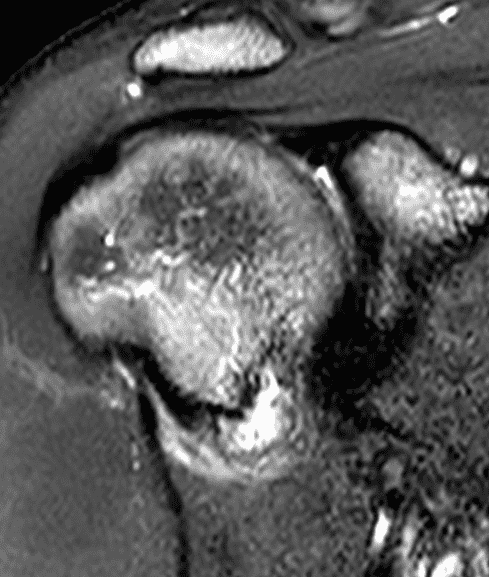

A 19 year old college baseball pitcher heard a “pop” after throwing a ball. Axial fat-suppressed proton density-weighted (1A and 1B), coronal fat-suppressed T2-weighted images (1C), and a Grashey projection radiograph (1D) images are provided. What are the findings? What is your diagnosis?

Figure 2: (2A) An axial image at the level of the humeral lesser tuberosity (LT) shows an intact subscapularis tendon (arrowheads). (2B) More inferiorly at the level of the humeral neck (HN), the direct muscular attachment of subscapularis (yellow arrows) is avulsed from the humerus together with the anterior band of the inferior glenohumeral ligament (red arrow), representing humeral avulsion of the glenohumeral ligament, a HAGL lesion. (2C) A coronal image through the anterior humerus shows the avulsed direct muscular attachment of subscapularis (yellow arrows), and the retracted end of the torn anterior band of the inferior glenohumeral ligament (red arrow). (2D) The radiograph shows a small, avulsed bone fragment of the humerus (red arrow), making this injury a “bony” HAGL (BHAGL) lesion. He failed 3 weeks of conservative management, with persistent 7/10 shoulder pain and was managed operatively with a lesser tuberosity repair. 6 months later, after taking a hiatus from baseball, his pain was completely resolved.